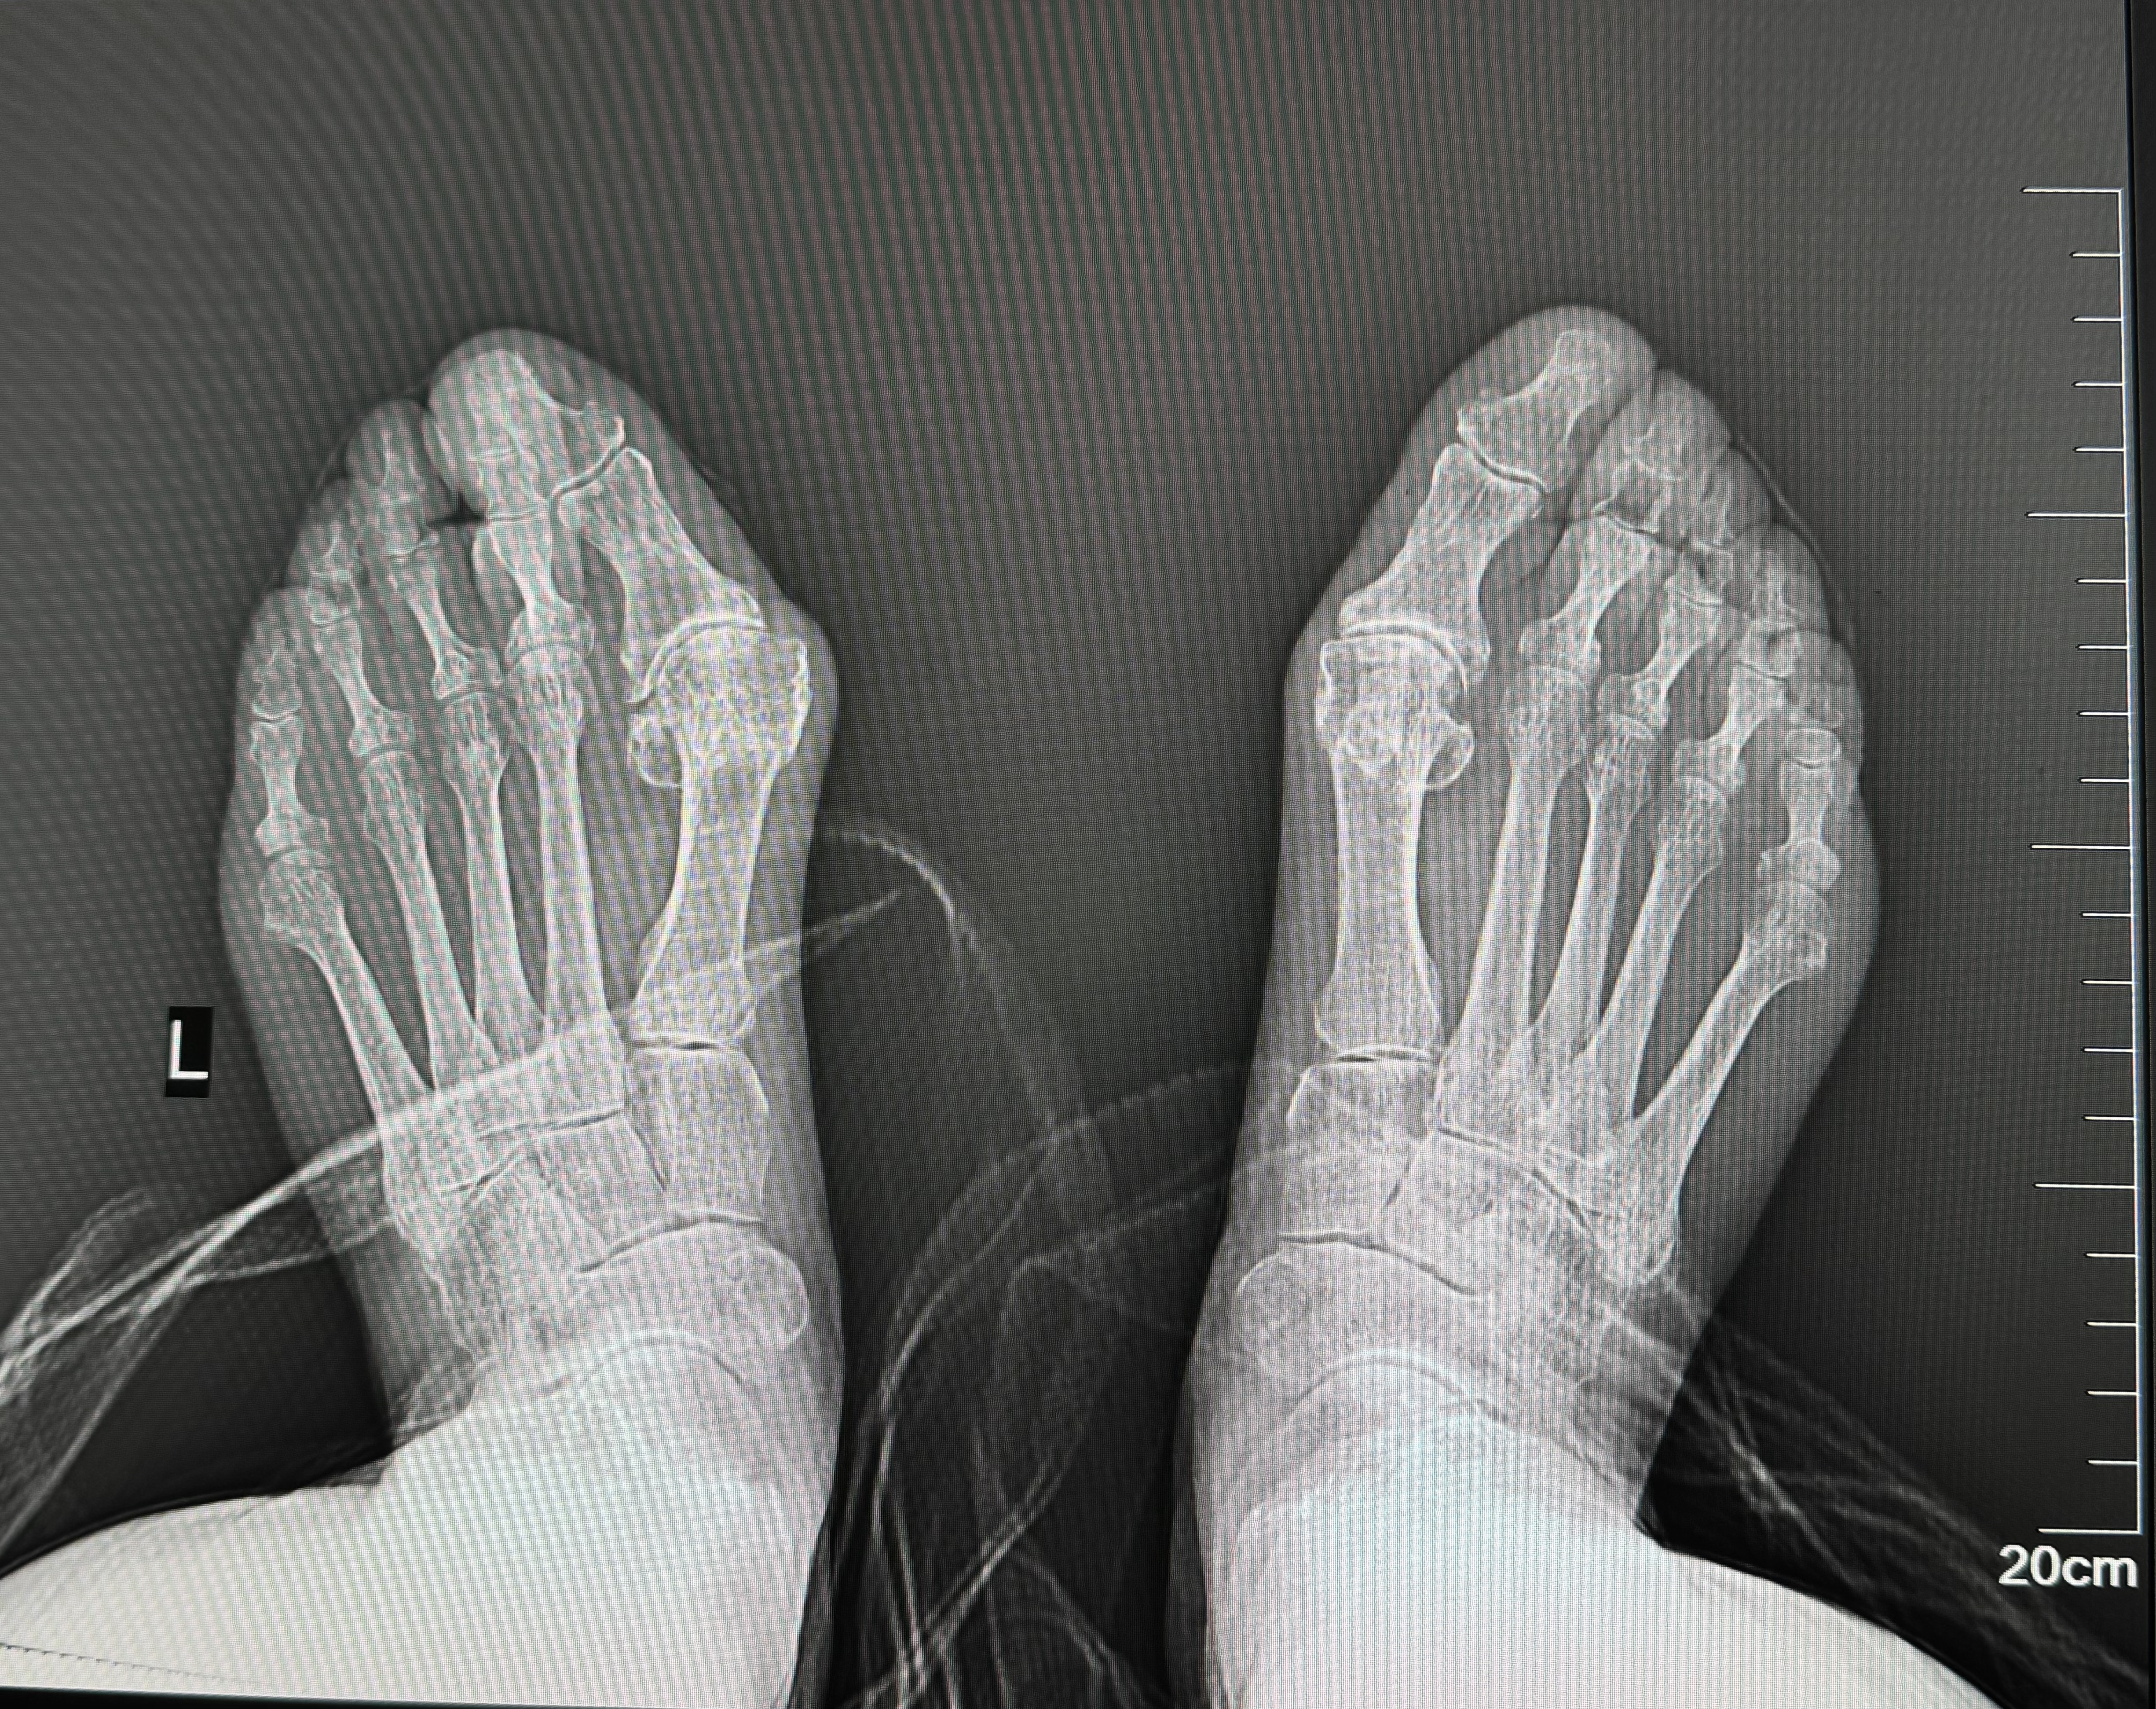

术前影像图

吕红兵完善相关检查发现,患者左足踇趾挤压第2趾,第1跖骨头处压痛明显,诊断为左足第一跖趾关节炎、左足踇囊炎,系重度踇外翻,拟行手术治疗。

和患者充分沟通并完成术前准备后,在科主任姬传磊的指导下,吕红兵凭借精湛的技术,顺利行微创踇外翻截骨矫形术,手术耗时较短,患者3天后下地行走,1周后顺利出院。

9月1日上午,患者来院复查,恢复情况较好,走路姿态基本正常,目前已回归到正常生活中。